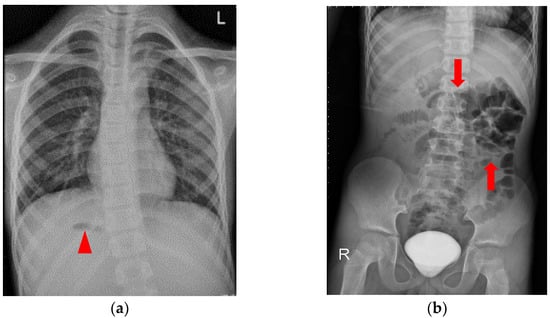

2. Detailed Case Description